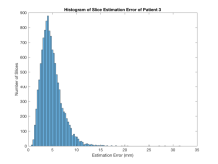

We have tested our approach on 85 randomly selected and accurately segmented healthy adult brains, on a real-world use case scenario with 34 roughly delineated fetal brain MRI scans and on 60 low-dose thorax CT scans with no organ specific segmentation. SVRNet’s average prediction error for these datasets is respectively 5.61.07mm, 7.74.80mm, and 5.92.43mm. We evaluate 3D reconstruction performance using the Peak Signal-to-Noise Ratio (PSNR) and prediction error as average distance in mm between ground truth locations and predicted locations , i.e., .

Exp. 3: Adult thorax data: To show the versatility of our approach we also apply it to adult thorax scans. For this experiment no organ specific training is performed but the whole volume is used. We evaluate reconstruction performance similar to Exp. 1 and prediction performance when is projected on an external plane, comparable to X-Ray examination using C-Arms. The latter provides insights about our method’s performance when applied to interventional settings in contrast to motion compensation problems. 60 healthy adult thorax scans were randomly selected, 51 scans used for and nine scans used for . Each scan is intensity normalised and resampled in a volume of with spacing . Using the Fibonacci sampling method, 25 sampling plane of size , evenly spaced between -50 and +50, were rotated over 500 normals. Training took approximately 20 hours for 60 epochs. Fig. 4c shows an example reconstruction result gaining 28dB PSNR with additional SVR. prediction takes approx. 20 ms/slice for this data.